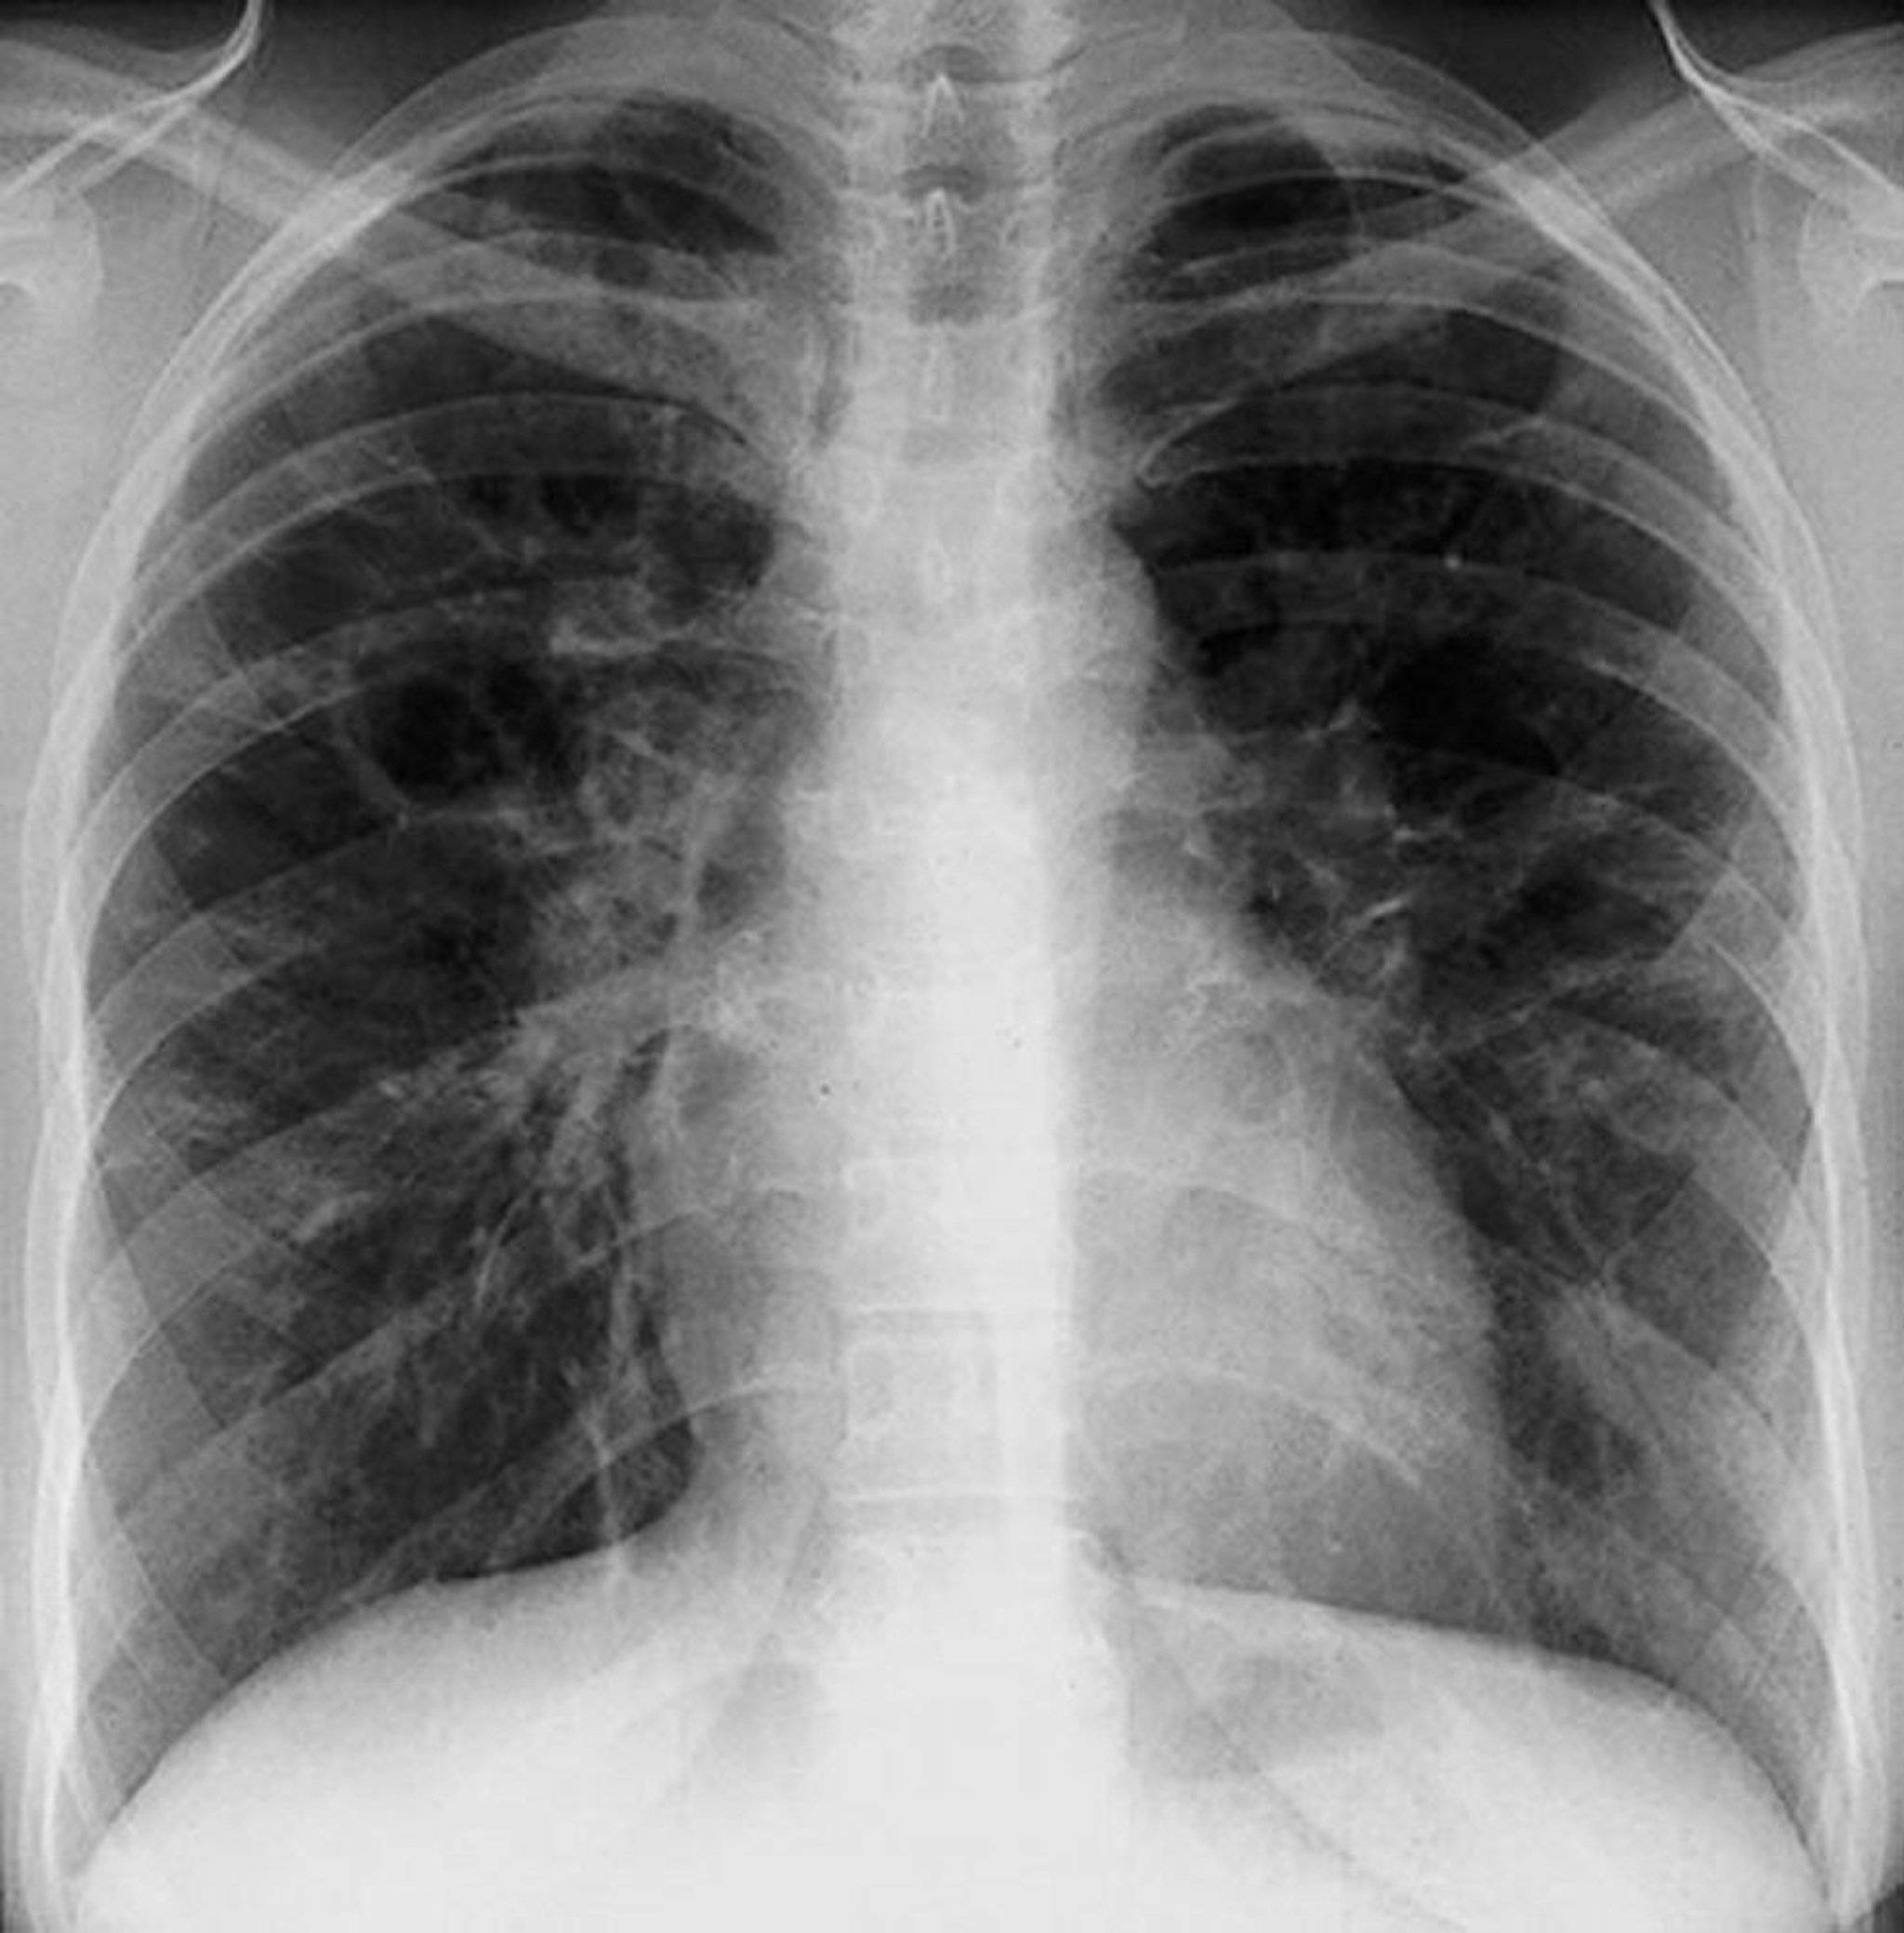

Sarcoidose (estágio III)

Infiltrados intersticiais difusos sem adenopatia hilar na sarcoidose em estágio III.

By permission of the publisher. De Tanoue L, Elias J. In Bone's Atlas of Pulmonary and Critical Care Medicine. Edited by J Crapo. Philadelphia, Current Medicine, 2005.